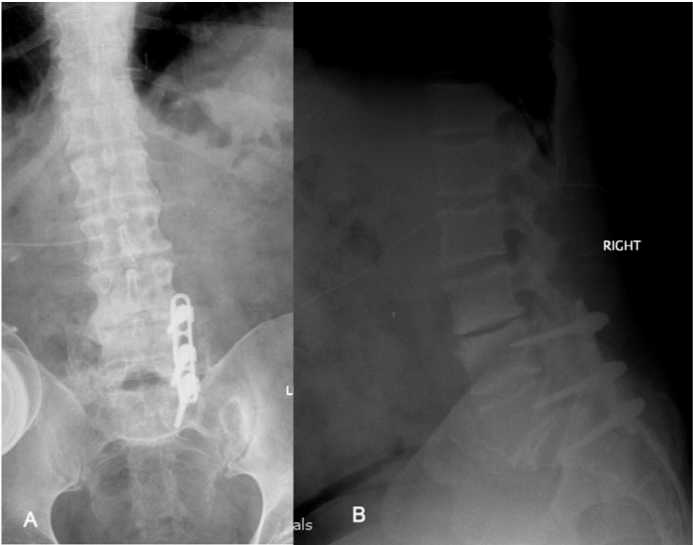

This was clearly a surgical target correlated with the patient’s symptoms and clinical findings. However, there were significant concerns about revision surgery through previous posterior approach because of previous complications; in particular deep infection for which part of the implants had been removed, albeit many years previously. Anterior surgery was not without significant risks because of his size. A relatively new but established technique, using trans-psoas approach via a small incision through loin was exploited. Through this approach, both aforementioned concerns were circumvented whilst it allowed discectomy and indirect decompression and fusion. It restored the lateral recess and foramina height, by restoring the disc height when an oversized cage packed with bone graft placed in the disc space after discectomy. This was then stabilised by a plate and two screws inserted parallel to endplates (Figure 3). The back pain significantly subsided soon after the surgery and the patient returned to his previous pain control regime. O.D.I. score decreased from 84 pre operatively to 46 six weeks post operatively and maintained at the same levels two years after this intervention. VAS back was 10 and 5 while VAS leg was 7 and 6 respectively. On the latest follow up, 2 years following surgery, he remained stable with regards of his symptoms with the IT morphine pump controlling the leg pain.

Figure 3 A) AP post-operative (2 years) view of the lumbar spine demonstrating evidence of solid L3-L4 interbody fusion. B) Lateral post-operative (2 years) view of lumbar spine demonstrating restored disc height and subsequently restored foramina height using an interbody cage stabilised by a plate and two screws parallel to endplates.